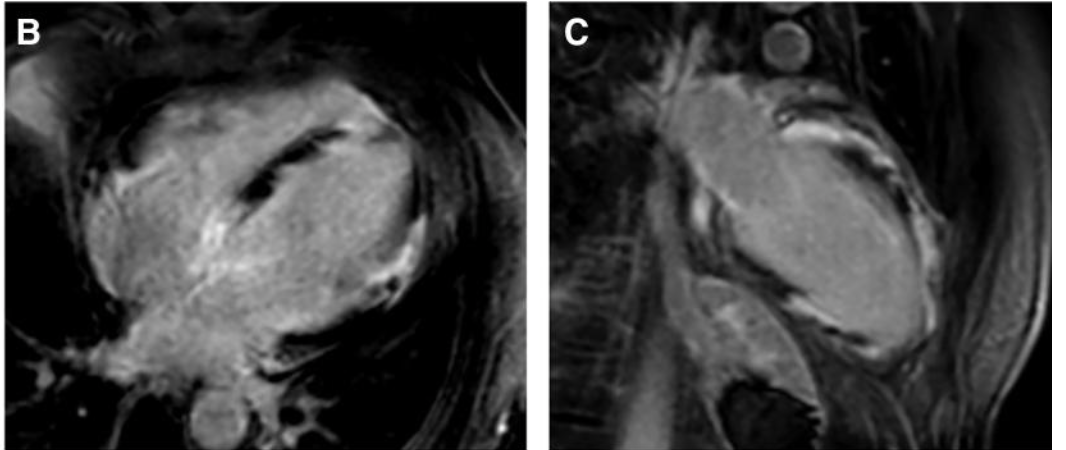

Granulomatous Cardiomyopathy

Phenotypes of cardiac sarcoidosis: